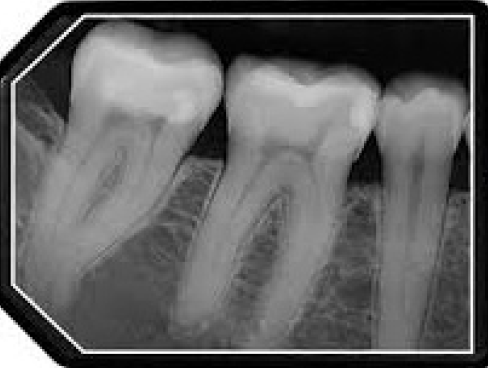

The purpose of the intraoral periapical examination is to obtain a view of the entire tooth and its surrounding structures, as in Figure 1. Two exposure techniques may be employed for periapical radiography: the paralleling technique and the bisecting angle technique. The paralleling technique is the preferred method. This technique provides less image distortion and reduces excess radiation to the patient. The paralleling technique should always be attempted before other techniques. The bisecting technique can be employed for patients unable to accommodate the positioning of the paralleling technique. Candidates may include those with low palatal vaults and children. Disadvantages to the bisecting technique include image distortion and excess radiation due to increased angulations involving the eye and thyroid glands. Regardless of the technique, however, the rules of radiography referred to earlier must be followed.

Figure 1 - Periapical Image

Figure 1